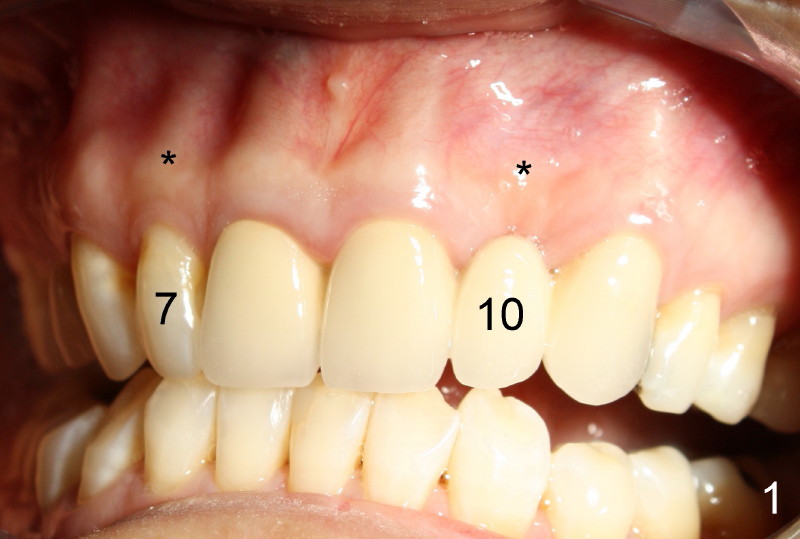

Segmental Osteotomy for Misplaced Implant

This corrective surgery was performed by Dr. Bernee Dunson.

Xin Wei, DDS, PhD, MS 1st edition 12/21/2011, last revision 12/23/2011